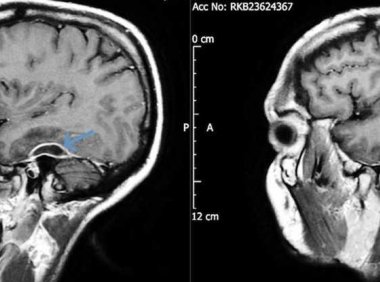

在一份新发表的病例报告中,医生详细描述了一名31岁的健康男子在昏倒后如何被救护车送往医院急诊室。 一到医院,他就癫痫发作,体格检查显示他神志不清,昏昏欲睡,神志不清。 后来,他透露,他已经有好几天感到头痛和恶心,在这段时间里,他很难记住别人的名字,更不祥的是,他承认在过去的五年里,他感到“间歇性的左耳疼痛和听力丧失”。 当医生对这名男子的头骨进行CT扫描时,他们发现他大脑周围的组织中有脓肿,他一只…... 启风